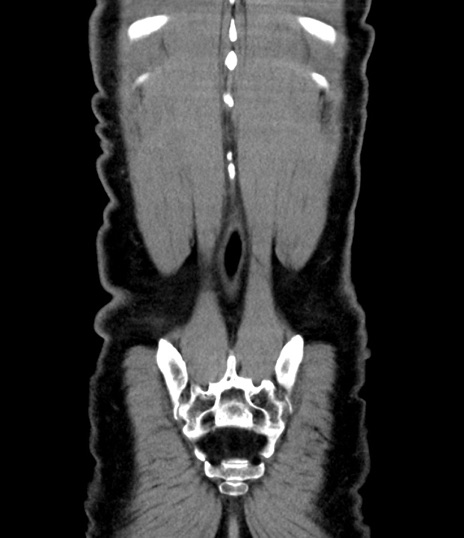

症例8(冠状断像)

【症例】 60歳代男性

【主訴】 黒色吐物

【現病歴】 4日前から嘔気自覚、2日前の朝食後にも嘔気あり、自分で手で嘔吐反射起こし嘔吐したところ血が混ざっていたため受診。

【既往歴】 5年前汎発性腹膜炎を伴う急性虫垂炎で手術、高血圧、前立腺肥大症、高脂血症

【身体所見】 腹部正中に手術癩痕あり 腹部平坦・軟圧痛なし膨満感あり

【データ】WBC 8400、CRP 4.54